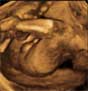

Ecografía 4D en la semana 20: Niña bostezando

Las ecografías en 4D permiten contemplar la misteriosa vida del feto, sus movimientos, tanto faciales como corporales, reflejos, como la succión... En esta imagen el bebé de 20 semanas de embarazo, una niña, bosteza dentro del útero materno,

Niña bostezando

Cara de perfil con la boca abriéndose: se aprecia parte del brazo y el cordón umbilical.

El bebé casi saca la lengua en el bostezo.